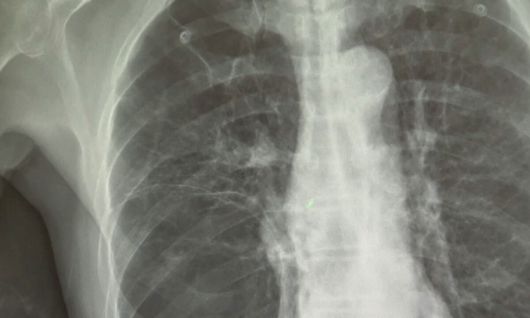

폐암 X-RAY. 연합뉴스 |